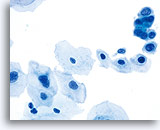

在传统的巴氏涂片上,细小的异常细胞通常会与 HSIL 相伴出现;这些细胞通常会被包裹在粘液中,或“隐藏”在背景物质内的细胞团内。由于在采用 ThinPrep 系统时,粘液和细胞碎片会经过分散处理,因此由该系统处理的标本会看起来有所不同。在使用倍镜读片时,细小的 HSIL 细胞会以单个细胞或以小细胞团的形式,在细胞的沉积背景中“凸显”出来。这些细胞应能提醒您:应更加密切地关注所呈现出的细胞物质,并查找是否有更多可供诊断的高度上皮细胞团。只要在低倍镜下看到这些细小的单个细胞或细胞团,就可在高倍镜下对这一部分玻片进行“筛查”。ThinPrep 系统的分散处理流程不会使真正的上皮细胞团发生破碎(因为高度病变存在异型性),并将会呈现出更多的单个细胞,注意到这点是至关重要的;这些是寻找病变细胞的“线索”。

对于 ThinPrep® 涂片检测,HSIL 的诊断标准如下: 单个细胞(HSIL 最重要的标准)是不对称三维胞核结构异型的表现。为掌握 HSIL 诊断,必须对此概念有明确的理解。不良胞核的结构将发生异型变化;对于这些胞核而言,只有对单个细胞的焦距进行上下控制,才可对这些胞核做出彻底的诊断。此概念是最难以在书本图片(二维页面)上展示的;然而,这却是最为重要的。

试想想对一个微缩的花椰菜、握紧的拳头、棒球或扁桃腺的焦距进行上下对焦。葡萄干的表面看起来像什么?正常胞核的形状相对较圆或呈椭圆形,并且其表面也是平滑的。不良细胞将具有凸起、凹陷、褶皱、裂纹和奇怪的隆起。这些非常明显的异型性是异生性(特别是 HSIL)的基本特征;而由于传统的细胞涂片在固定和染色过程中会存在各种干扰物质,上述的细节往往会在传统的细胞涂片丢失 , 这样令传统涂片的诊断能力造成限制。

这些三维细胞结构的异型性可与简单的“不规则细胞核轮廓”区别开来;在 ThinPrep® 玻片上,这些将是良性细胞的一种特征表现。由于是二维的, 由于是二维的,当检查员在显微镜下上下对焦时,这些“褶皱”像裂缝或山脉般难以在胞核中心被追踪,这样会为无经验者做成相类似的假像。

在玻片上,并不是每个不良细胞都会呈现出这些三维结构的异型性;但是,在这些玻片上,这些异型性至少会在一些细胞中较为明显。显然,染色质量直接关系到是否能够看到胞核“内部”。(与传统的巴氏涂片相比,所有的 ThinPrep® 涂片检测都使得细胞变化更为明显;但如果对反应物进行过度染色,或有轻微腐败,都将对这种最为重要的评估标准造成直接影响)。此外,与细胞凹陷或简单的褶皱(会达到胞核的全部宽度,具有“相似本体”,并会造成一定的难度)相比,这些三维结构的缺陷应该是不对称的。由于这些胞核的三维异型性能够得到放大,因此能够为 HSIL 诊断提供依据。